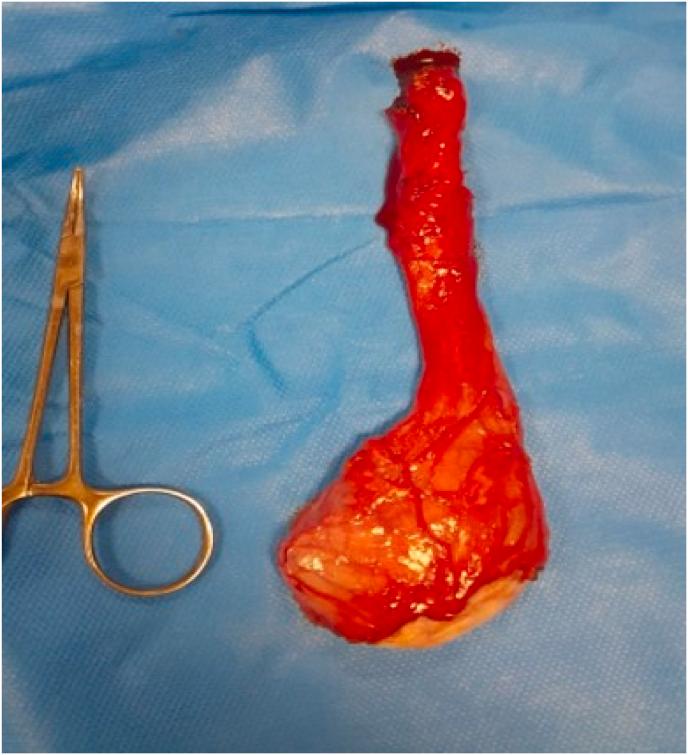

This case report presents a 61-year-old male patient diagnosed with high-risk prostate cancer who underwent hormone therapy and radiotherapy. Three years after beginning treatment, rising prostate-specific antigen (PSA) levels led to a PET CT scan, which identified isolated metastases in the left testicle. The patient then underwent a radical orchiectomy. One-year follow up revealed undetectable PSA and no evidence of any metastases. The significance of this case lies in the uncommon occurrence of testicular metastasis from prostate cancer, particularly when presenting in isolation after a prolonged period following hormone therapy and radiotherapy.

本病例报告介绍了一名61岁的男性患者,他被诊断为高危前列腺癌,接受了激素治疗和放射治疗。治疗开始三年后,前列腺特异性抗原(PSA)水平升高,于是进行了PET CT扫描,结果发现左侧睾丸有孤立性转移灶。该患者随后接受了根治性睾丸切除术。一年的随访显示PSA检测不到,且无任何转移迹象。本病例的意义在于前列腺癌发生睾丸转移的情况不常见,尤其是在激素治疗和放射治疗后的较长时间后单独出现。